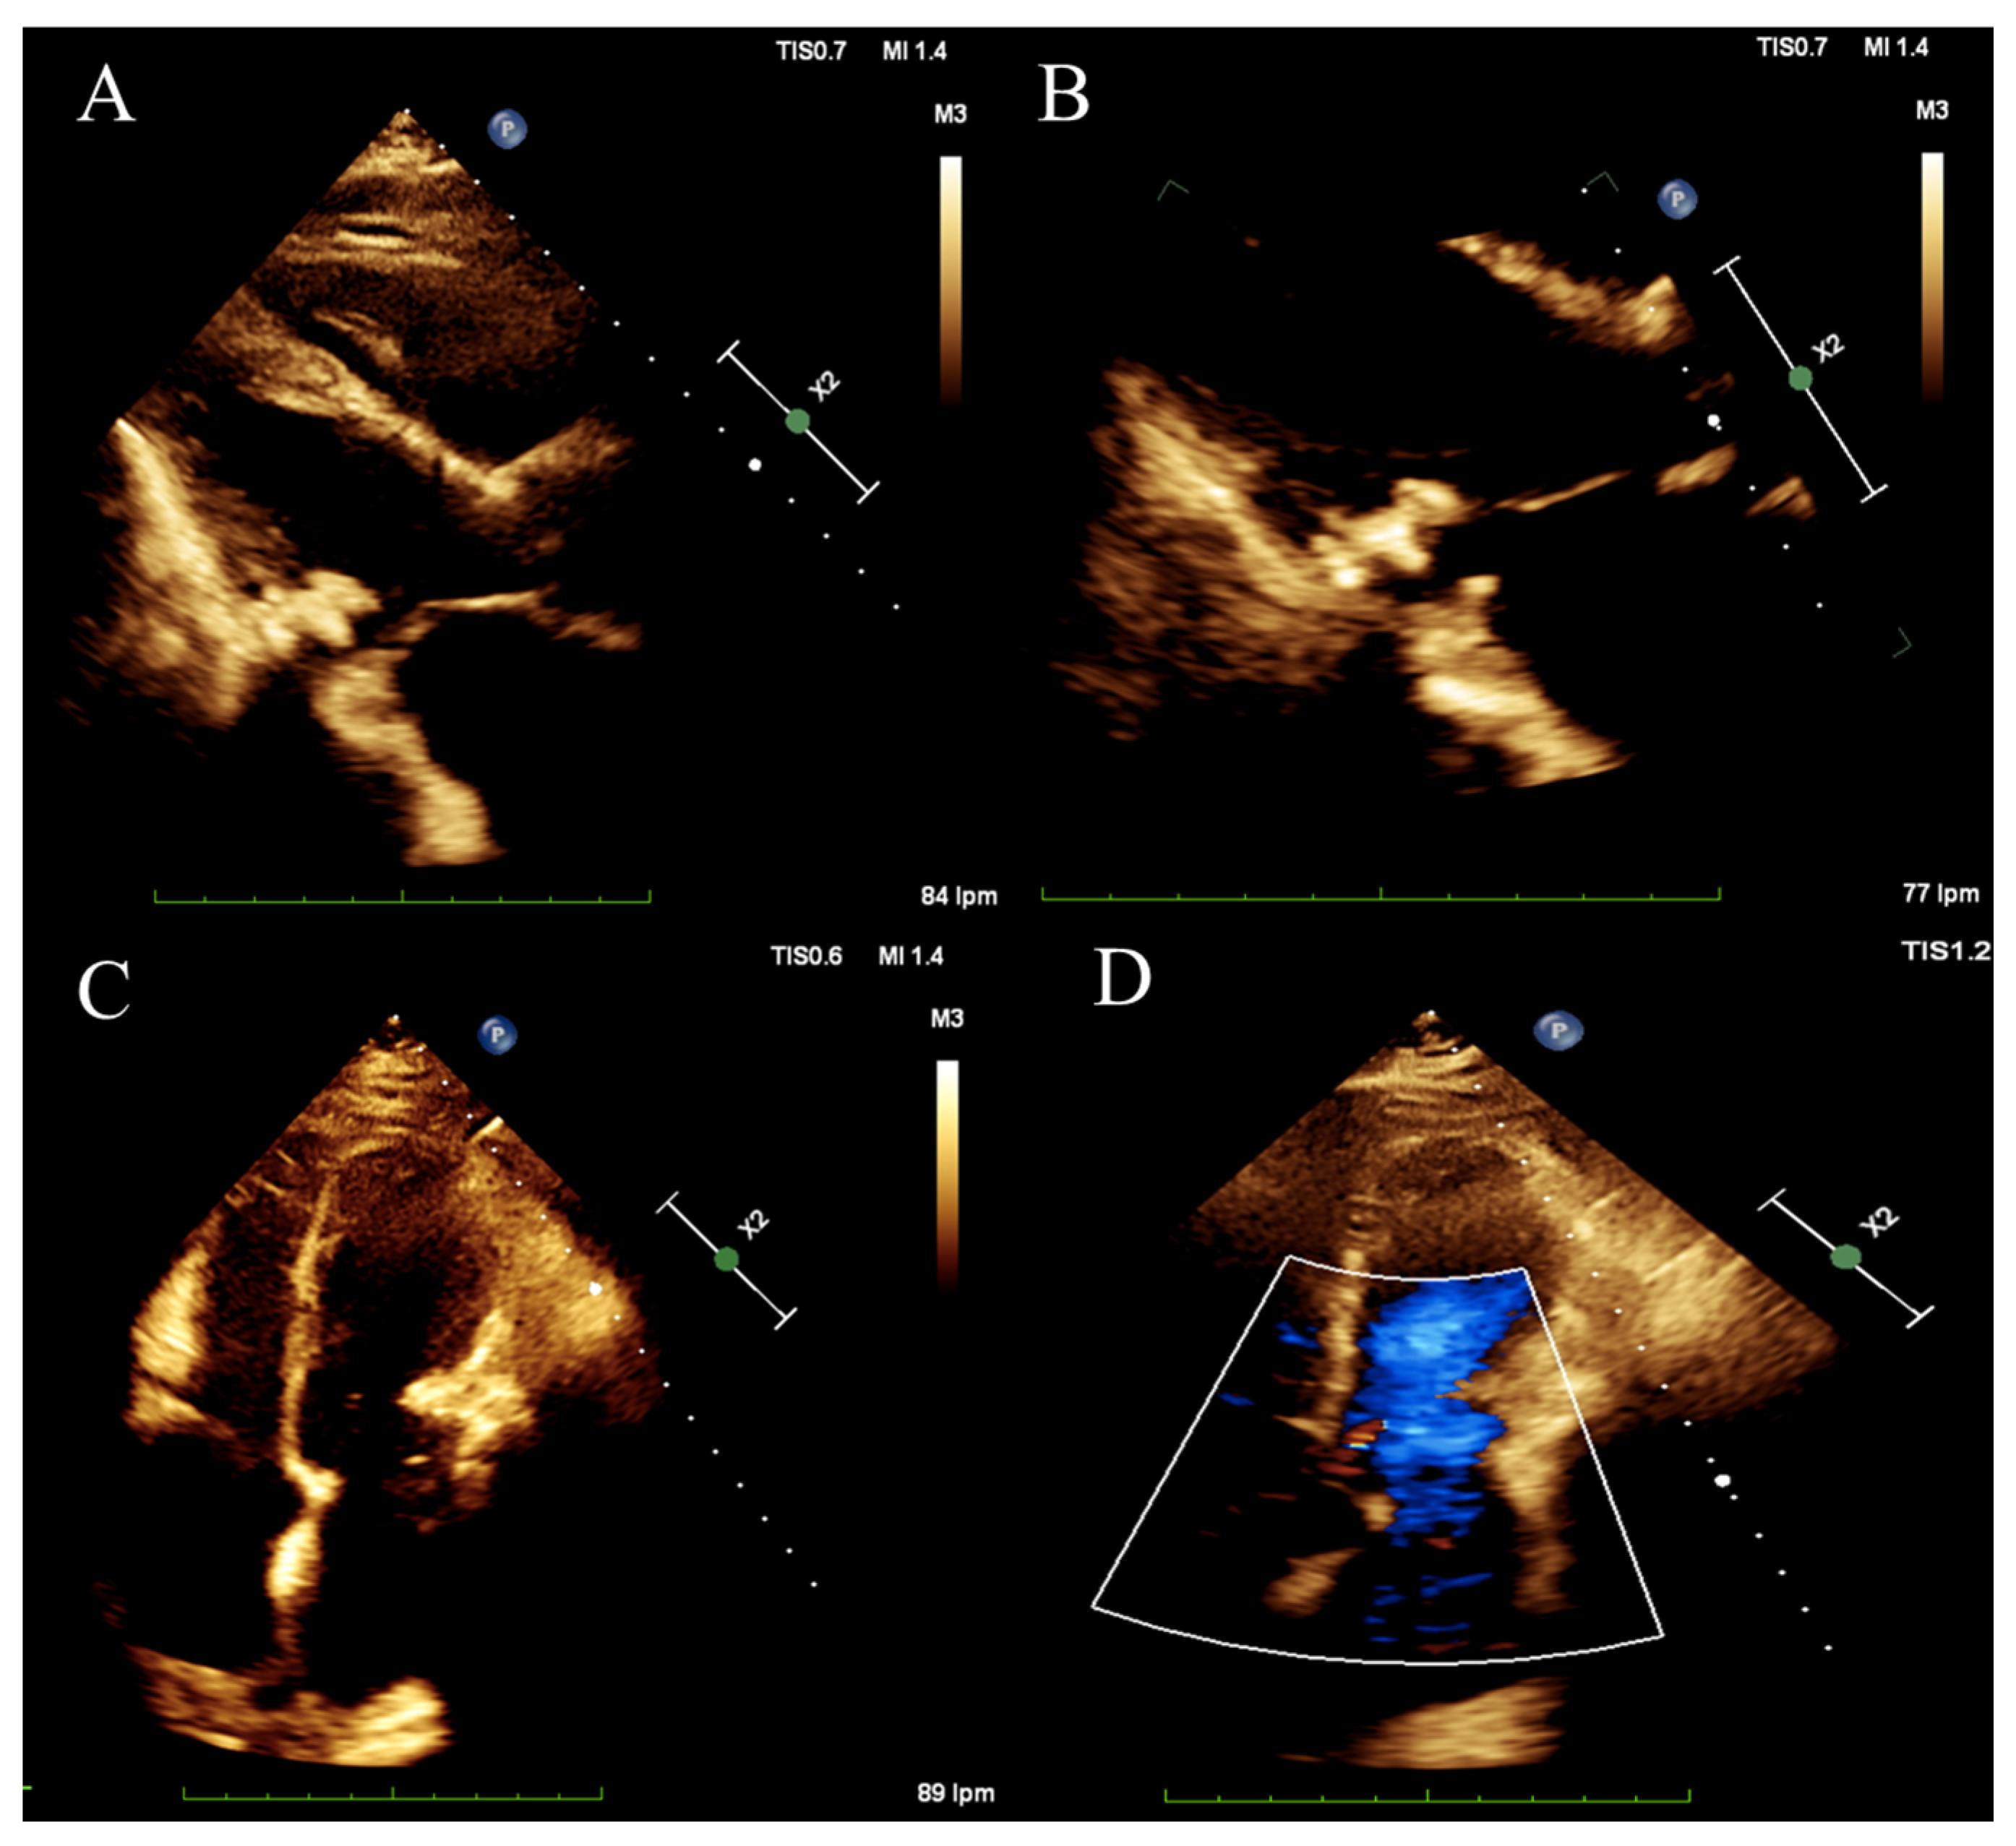

2. Case Presentation

2.3. Clinical Findings